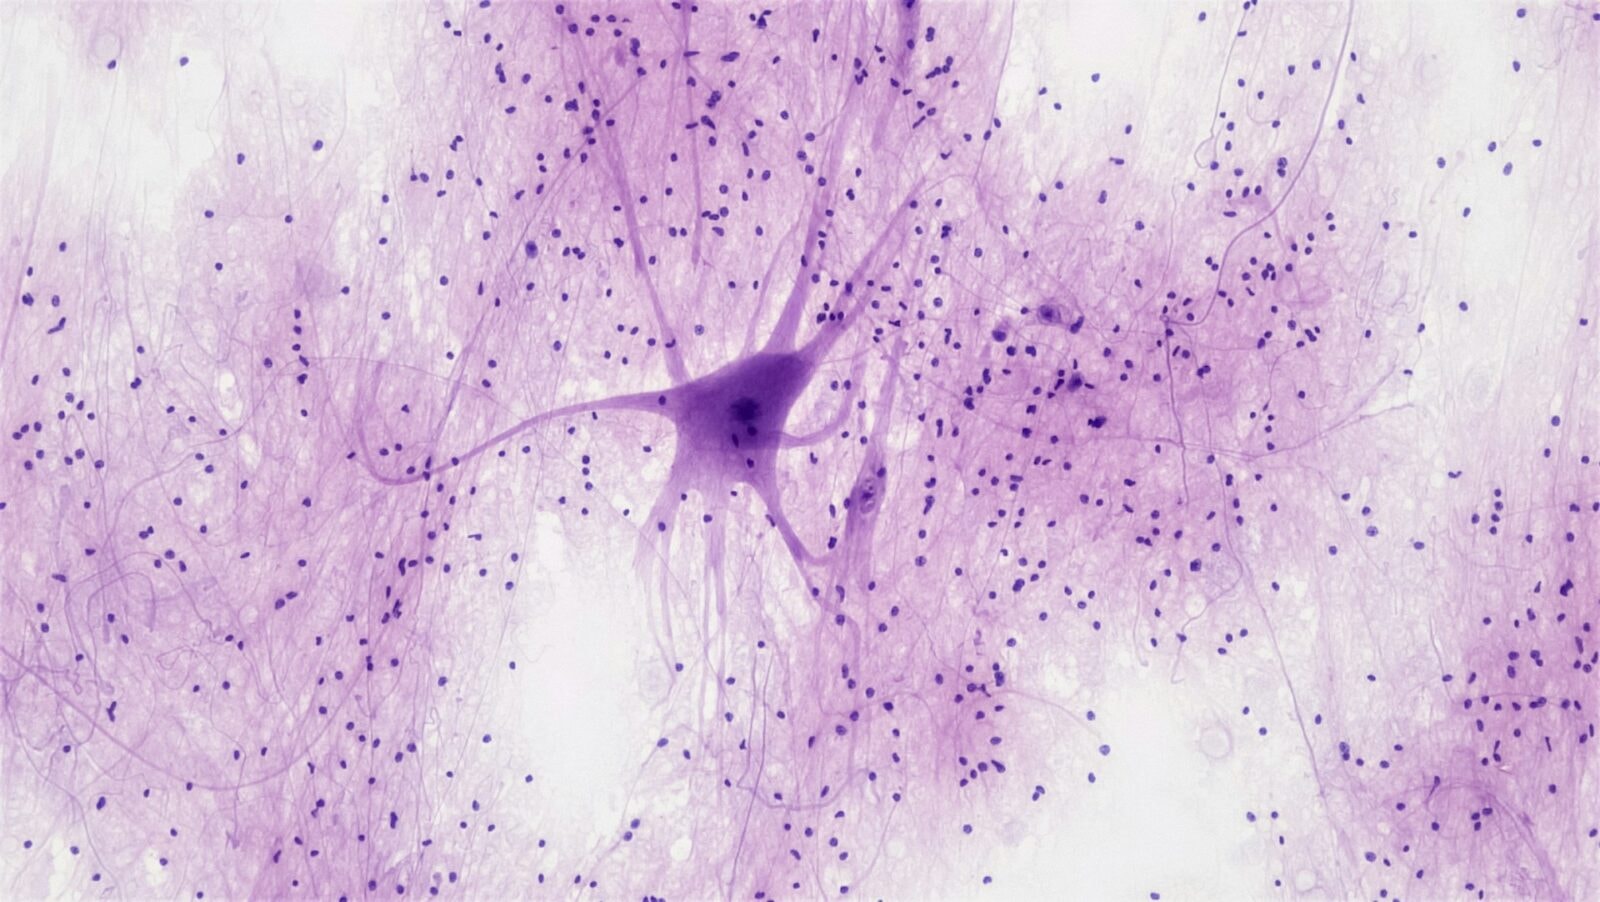

Tradycyjne zamrażanie powoduje powstawanie kryształków lodu, które niszczą komórki i prowadzą do nieodwracalnych uszkodzeń. Witryfikacja eliminuje ten problem, zamieniając płyny ustrojowe w amorficzną, szklistą substancję. W eksperymencie dr Germana tkanki mózgowe schłodzono do -196oC w ciekłym azocie, a następnie przechowywano w temperaturze -150oC. Po tygodniu fragmenty hipokampu powoli rozmrożono do -10oC, co pozwoliło uniknąć szoku termicznego i zachować strukturę komórkową. Wyniki wykazały brak krystalizacji oraz pełną regenerację aktywności elektrycznej.

Jednym z najbardziej intrygujących aspektów eksperymentu jest możliwość zachowania wspomnień. Hipokamp, na którym przeprowadzono badanie, odpowiada za konsolidację pamięci. Choć nie udowodniono jeszcze zachowania konkretnych wspomnień, to fakt, że synapsy i aktywność elektryczna zostały w pełni przywrócone, rodzi fascynujące pytania o potencjalne możliwości przechowywania informacji w stanie anabiozy. German podkreśla, że dalsze badania będą musiały zweryfikować, czy wspomnienia przetrwały proces witryfikacji, oraz czy możliwe jest ich odtworzenie po ponownym uruchomieniu aktywności mózgu.